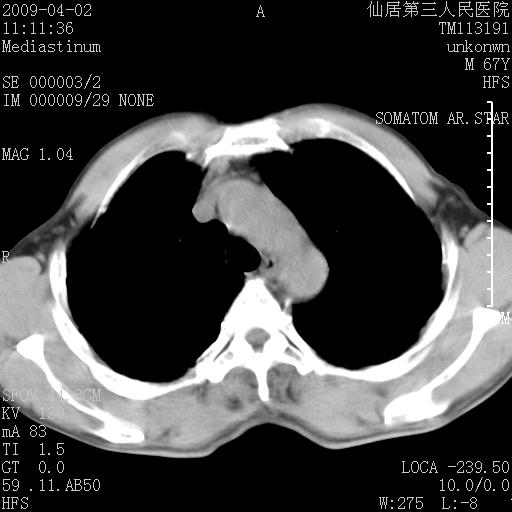

患者老年男性,乏力畏寒来诊,摄胸片示右下肺感染性病变,抗炎两周后复查胸片,无好转有进展。

后做ct平扫表现如下:

考虑右肺炎症可能性大,不除外细支气管肺泡癌

病灶呈蜂窝征,纵隔多个淋巴结肿大;肺泡癌需考虑

我认为普通的感染应该可以除外,间质性肺炎可能性较大,但如何解释纵膈的淋巴结肿大呢

考虑双肺间质性改变(间质纤维化?)伴右肺下叶感染。